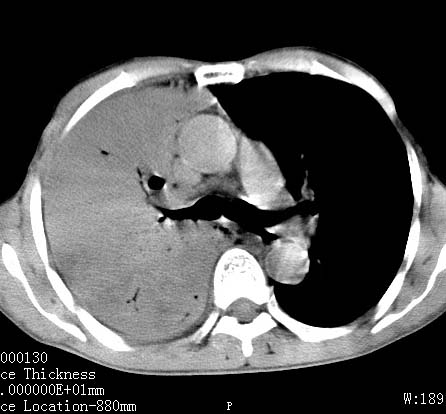

病人女 60岁 咳嗽 气促十余天,大叶性肺炎.

右肺上下叶均见 大片状密度增高影,边界清晰,其内可见支气管充气征,气管支气管通畅。纵膈略向右移位,其内无肿大淋巴结影。首先考虑炎性病变。不排除一些特异性的炎症。不知道发烧吗??wbc高吗??建议治疗后复查!!